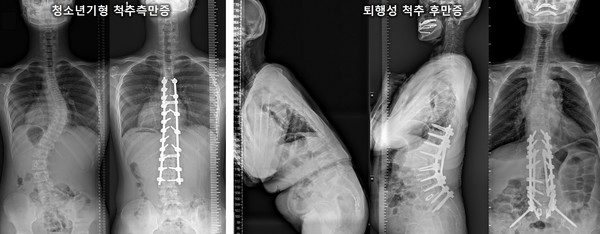

척추변형 질환 중에서도 청소년기에는 청소년기형 척추 측만증, 노년층에서는 퇴행성 척추 후만증이 주로 관찰된다. 뒤에서 보았을 때 옆으로 휘어 있다면 척추 측만증, 등이 뒤로 튀어나왔다면 척추 후만증이다. 진단은 병력청취와 함께 X-RAY를 통해 뼈의 이상 유무를 확인하고, 신경학적 문제나 디스크가 의심된다면 MRI를 병행해 보는 것이 좋다.

경희대병원 정형외과 이기영 교수는 “청소년기형 척추 측만증은 사춘기가 시작되기 직전부터 골격 성장이 완료되는 시기, 통상적으로 11~18세에 나타나는 척추 측만증으로 척추가 휘어져 몸이 좌우로 기울거나 회전해서 틀어져 버린 3차원적 변형 상태를 의미한다”며 “초기에는 뚜렷한 증상을 보이지 않지만, 성장을 이루는 속도와 변형이 맞물리게 되면 급격히 측만 정도가 심해질 수 있어 전문 의료진의 정기적인 진찰과 함께 적절한 진단 및 치료가 병행되어야 한다”고 말했다.

노년층에서 관찰되는 퇴행성 척추 후만증은 주로 쪼그리고 앉은 자세로 수십 년 동안 농사일을 했거나 주방에서 일을 많이 한 여성에게 많이 발생하는 것으로 알려져 있다. 걸을 때 몸이 앞으로 구부러지면서 생기는 보행 장애와 함께 물건을 들어올리기 힘들고, 경사진 언덕이나 계단을 올라가는 데 힘이 드는 것이 대표적인 증상이다.

그러나 운동 치료 및 보조기 치료 등의 보존적 치료에도 불구하고 퇴행성 척추 후만증의 증상이 심하다면 후만된 요추부의 분절에 전방, 후방, 또는 전후방 도달법을 이용하여 교정하는 수술적 치료를 적극 고려해 보는 것이 권장된다.